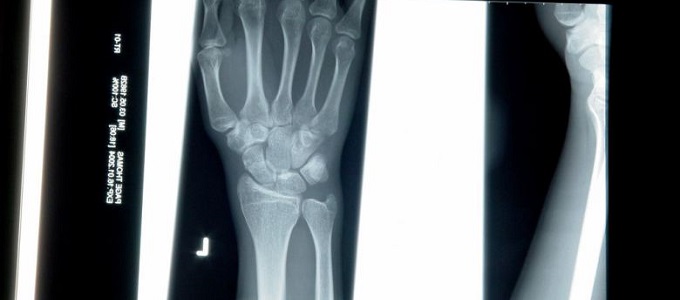

A gépek már ma is nagy szerepet játszanak az egészségügyben. Az MRI letapogatók betekintést nyújtanak a test belsejébe, a vérminták elemzése is automatizált, az emberi tudás azonban mindig szerves része volt a folyamatnak. Ha egy felvételen árnyékot látnak, az onkológus állapítja meg a jelentőségét. Az orvosok azonban sokszor elfoglaltak és túlterheltek, ami hibázáshoz, vagy az árulkodó tünetek feletti elsikláshoz vezethet. Ha a számítógépekkel sikerül megismertetni az egészségügyi fortélyokat, talán felgyorsíthatják, sőt akár alaposabbá is tehetik a diagnózisok felállítását.

Vegyünk egy mellrák vizsgálatot. A diagnózis felállításához jellemzően három forrás szükséges: röntgen, MRI és ultrahang. Ezek keresztvizsgálata munka- és időigényes, de nem a mély tanulással. Bradley és munkatársai elkészítettek egy prototípus rendszert, ami automatikusan elvégzi a keresztvizsgálatokat, felfedve a különböző utalásokat, összefüggéseket. A rendszert októberben mutatják be egy Münchenben megrendezésre kerülő nemzetközi számítógépes gyógyászati konferencián.

Az izraeli Tel Aviv Egyetem kutatói is alkalmazzák a mély tanulást a mellkas röntgeneknél. Eddig rendszerük elsajátította a szív megnagyobbodás és a tüdő körüli folyadék felgyülemlés diagnosztizálását. Az Egyesült Államokban a Maryland-i Bethesda Klinikán hasonló módszerekkel észlelik a gerinc körüli rákos elváltozásokat. Mindkét csoport a legújabb észlelési algoritmusokkal egyenértékű, vagy esetenként jobb eredményeket ér el. A kérdés azonban, hogy az orvosok, vagy a betegek elfogadják-e valaha is a gépek véleményét? Bradley szerint ez a rendszer legnagyobb gyengesége.